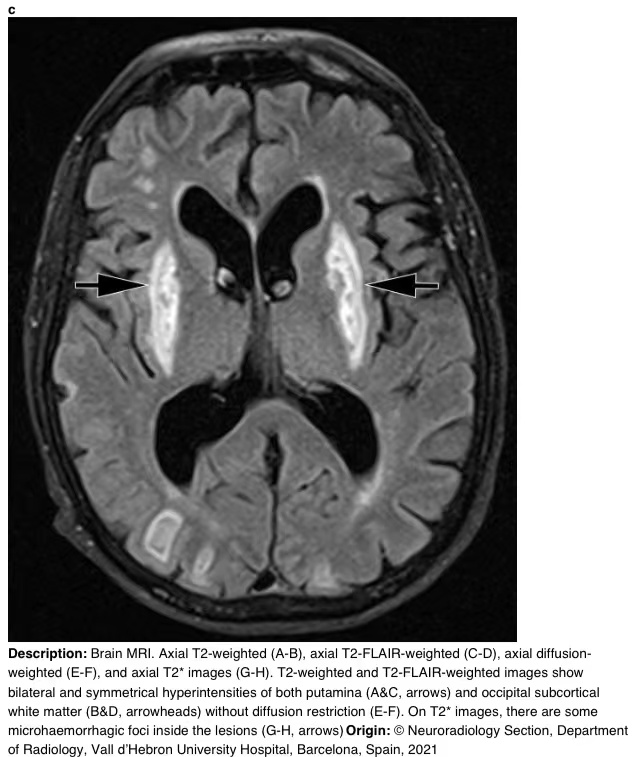

在16天的随访中,脑部MRI显示壳核和枕下皮质下白质上对称的T2/FLAIR高信号。T2图像显示病变内有微出血(图3)。

图3 a-h 脑部核磁共振成像。轴向T2加权(A-B)、轴向T2 FLAIR加权(C-D)、轴向弥散加权(E-F)和轴向T2图像(G-H)。T2加权和T2 FLAIR加权图像显示双侧和对称的壳核高信号(A和C,箭头)和枕下皮质下白质高信号(B和D,箭头),无弥散限制(E-F)。在T2图像上,病变内有一些微出血病灶(G-H,箭头)。